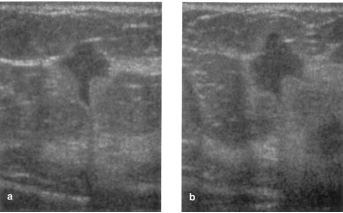

Paciente do sexo feminino, 56 anos, recebeu laudo da sua mamografia anual de rastreamento, com classificação BI-RADS 0, justificada por assimetria focal no QSL da mama direita. Na ecografia complementar, observou-se o achado da seguinte imagem na topografia da assimetria descrita. Com base na análise das imagens, assinale a alternativa correta.